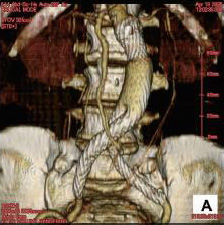

血管造影、IVR

血管造影・X線透視装置を中心に、超音波断層装置や世界初となるMRXO(MRI、血管造影、手術室一体型)システムを駆使した画像下での、カテーテルや高周波、レーザーなどを使用した血管内治療や気管、胆道の治療が中心となります。具体的には、原発性肝癌(消化器内科と共同)を中心とした癌への化学塞栓療法、転移性肝癌や子宮癌などへの動注化学療法のためのリザーバーシステム埋め込み(一般外科と共同)、閉塞性動脈硬化症や腎血管性高血圧、透析シャントなどに対する血管形成術(心臓血管外科や腎センターと共同)や大動脈瘤に対するステントグラフト治療(写真)、胃静脈癌に対する硬化療法、門脈圧亢進症による静脈瘤・肝性脳症に対する塞栓術や胆道ステント(消化器内科と共同)、喀血に対する塞栓術や気管・気管支ステント(呼吸器内科と共同)、外傷(肝、脾、腎、骨盤骨折、腸間膜損傷など)に対する塞栓術(高度救命救急センターと共同)、などが主な治療となります。

治療前腹部大動脈三次元CT

ステントグラフト治療後三次元CT